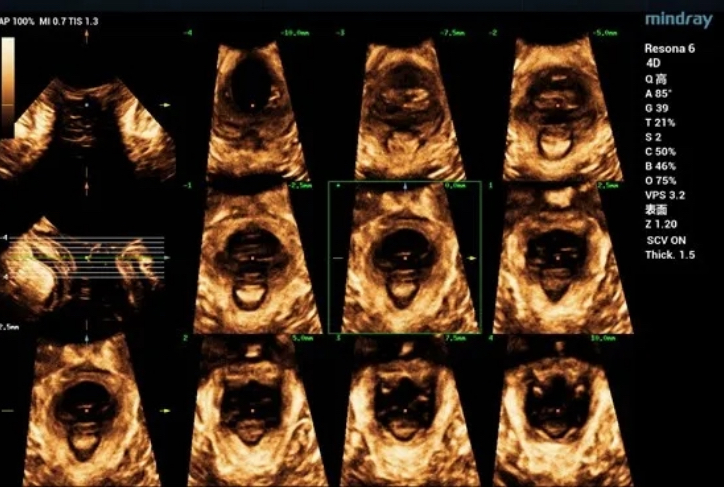

During maximal Valsalva maneuver, the bladder neck is 14mm below the pubic symphysis , the lowest point of bladder is 16.9mm below, the uterus is 7.3mm above and the rectum is 10.4mm below. The levator ani hiatus is 26.06cm2 (see Figure 2).

Figure 2 Two-dimensional ultrasonic measurement of pelvic floor structural parameters in Valsalva state

Figure 4 Three-dimensional ultrasound show levator ani hiatus area during Valsalva

Figure 5 Three-dimensional ultrasonic measurement of levator ani hiatus area